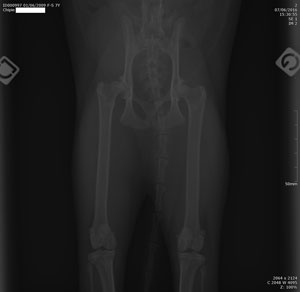

Le seul moyen de confirmer un diagnostic de dysplasie de la hanche est de réaliser une radiographie. Pour être interprétable, cette radiographie est très codifiée : le chat doit être allongé sur le dos, avec les pattes arrière maintenues bien parallèles. Une telle position est rarement acceptée spontanément par le chat, qu’il faut souvent tranquilliser ou endormir (anesthésie flash de quelques minutes).

Radiographie des hanches chez un chat.

Le vétérinaire examine ensuite sur la radio l’orientation des têtes de fémur par rapport au bassin ; il peut ainsi graduer la sévérité de la dysplasie. Il recherche aussi des signes de luxation ou d’arthrose, sous forme de proliférations osseuses autour de la cavité du bassin où s’insère la tête du fémur.